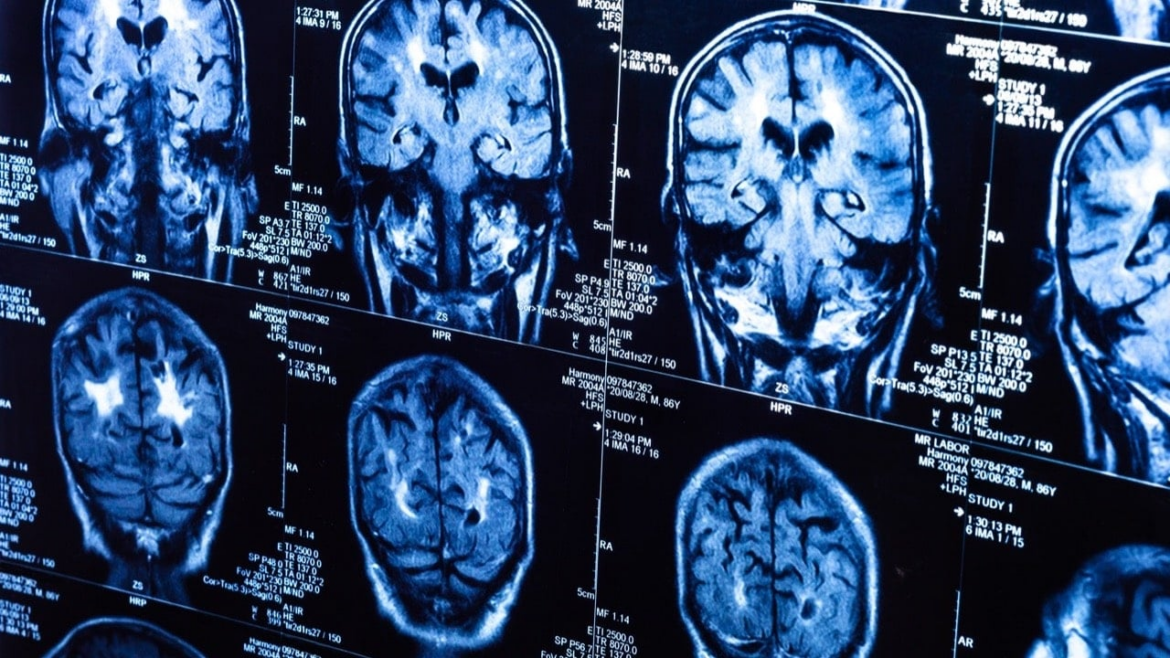

El sistema nervioso —que abarca el cerebro, la médula espinal, los nervios periféricos y los músculos— regula funciones esenciales como el movimiento, la memoria, el lenguaje y el pensamiento. No obstante, muchas enfermedades neurológicas pasan desapercibidas hasta que generan cuadros complejos. Según el Instituto Nacional de Ciencias Neurológicas (INCN), en el Perú la epilepsia encabeza las consultas, seguida por los accidentes cerebrovasculares, los tumores cerebrales, la enfermedad de Parkinson y las demencias.

En países como el Perú, las estadísticas difieren de los registros internacionales. Mientras en Europa y Estados Unidos predominan las enfermedades neurodegenerativas, aquí los casos más comunes están vinculados a factores endémicos. “La epilepsia es la principal causa de consulta, y muchas veces es consecuencia de cisticercosis o neurotuberculosis, dos enfermedades todavía presentes en el país”, detalla Escalante.

• Tumores cerebrales